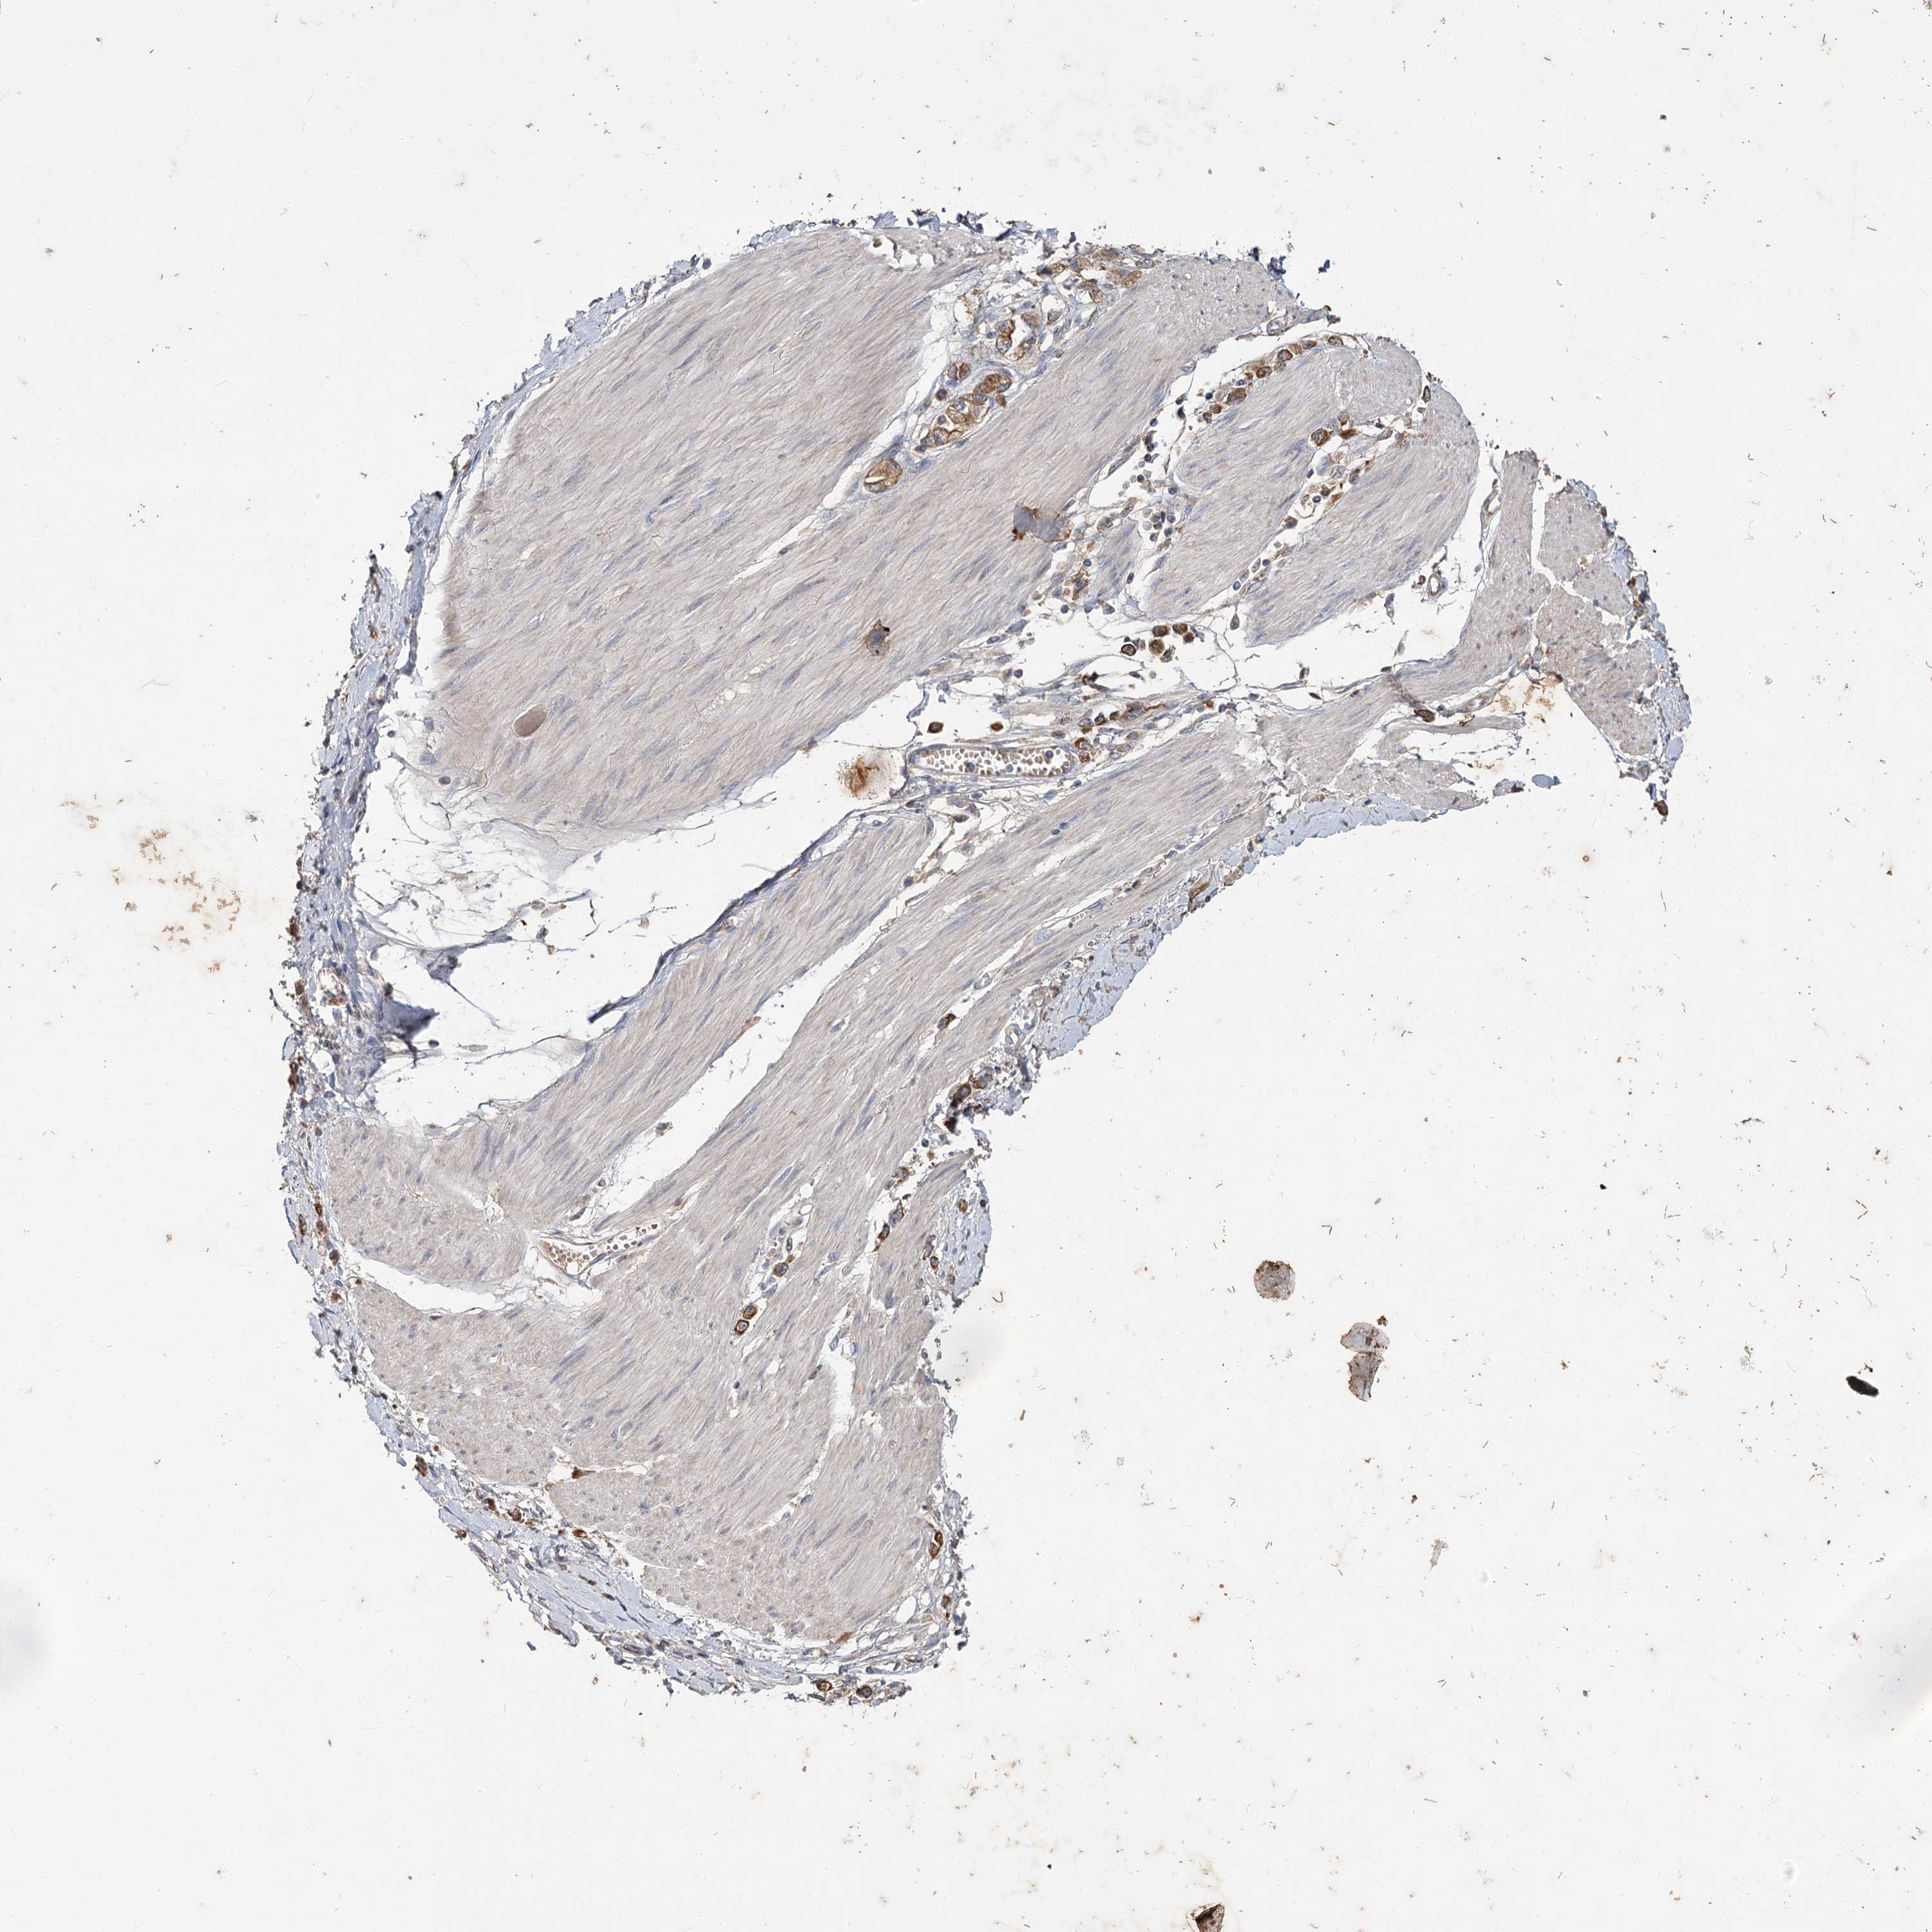

STOMACH CANCER - Protein expressioni

A mouse-over function shows sample information and annotation data. Click on an image to view it in a full screen mode. Samples can be filtered based on level of antibody staining by selecting one or several of the following categories: high, medium, low and not detected. The assay and annotation is described here.

Note that samples used for immunohistochemistry by the Human Protein Atlas do not correspond to samples in the TCGA dataset.

Antibody stainingi

Antibody staining in the annotated cell types in the current human tissue is reported as not detected, low, medium, or high, based on conventional immunohistochemistry profiling in selected tissues. This score is based on the combination of the staining intensity and fraction of stained cells.

Each image is clickable and will lead to virtual microscopy that enables deeper exploration of all samples and also displays staining intensity scores, fraction scores and subcellular localization as well as patient and tissue information for each sample.

Antibody CAB033437

Staining

High

Medium

Low

Not detected

Intensity

Strong

Moderate

Weak

Negative

Quantity

>75%

75%-25%

<25%

None

Location

Nuclear

Cytoplasmic/membranous

Cytoplasmic/membranous,nuclear

Adenocarcinoma, NOS